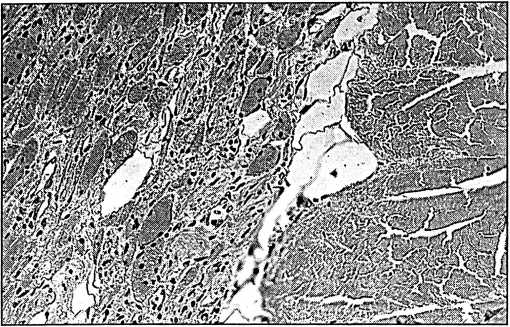

Послеоперационный период протекал тяжело, нарастали признаки полиорганной недостаточности (почечной, печеночной, церебральной и кишечной) с повышением миоглобинемии, уровня креатинина и азота мочевины крови в междиализный период. При УЗИ брюшной полости патологии не выявлено. На 6-е сутки после холецистэктомии и на 10-е сутки после поступления больной выполнена повторная КТ головного мозга, органов грудной клетки, брюшной полости и забрюшинного пространства. Обнаружено увеличение в объеме правой подвздошно-поясничной мышцы, которая оказалась больше левой в 2,5 раза. Явных различий в структуре мышечной ткани не определялось (рис. 4).

Рис. 4. Пациентка П. Компьютерно-томографическое изображение брюшной полости и забрюшинного пространства на уровне L1. П — правая, Л — левая подвздошно-поясничные мышцы.

Данная находка не позволяла исключить послеоперационное осложнение и явилась основанием для проведения правосторонней люмботомии. В фасциальном футляре правой подвздошно-поясничной мышцы обнаружен организовавшийся кровяной сгусток объемом 300-350 мл, мышца была размягчена и имбибирована кровью, признаков гнойно-воспалительного процесса в ходе ревизии не выявлено. Операция завершена дренированием фасциальной полости и забрюшинного пространства.